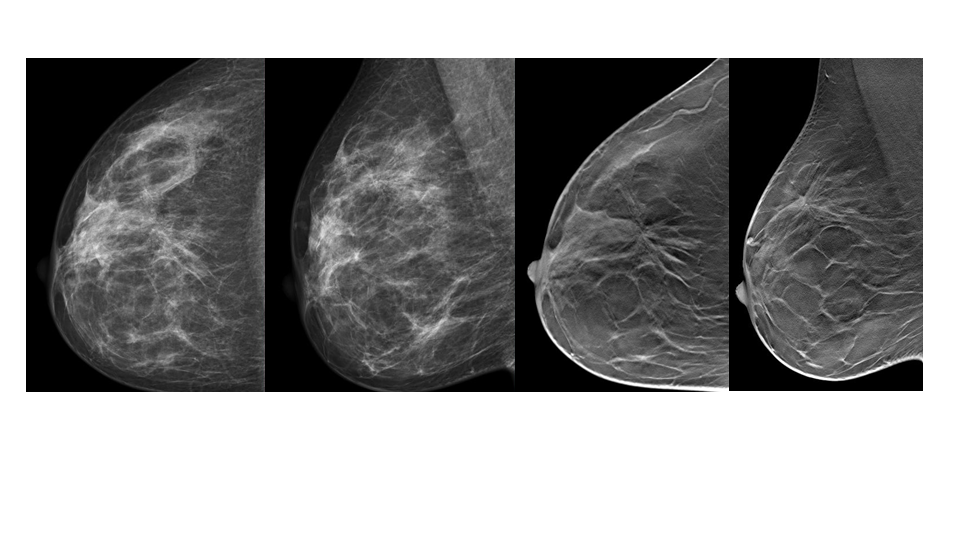

【病例】纤维囊性乳腺病伴纤维腺瘤形成 VS 乳腺增生病并间质硬化-3

【病例】纤维囊性乳腺病伴纤维腺瘤形成 VS 乳腺增生病并间质硬化-4